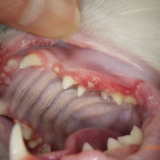

これは重度の歯周病があること示しており、抜歯の対象となります。歯石の付着が多かった左側については、下図黄色矢印のように歯の根の表面が欠けておりました。

左第2,3前臼歯(第1前臼歯は欠歯)黄色矢印が外部吸収